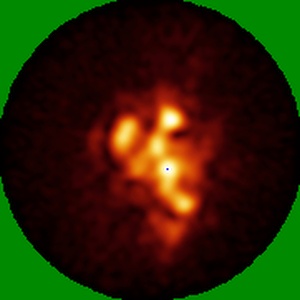

Polyclonal immune complex of Fab binding the H1 HA from serum of donor 7 at day 14

Single-particle25.0 Å

Sample: Polyclonal immune complex of Fab binding the H1 HA from serum of donor 7 at day 14

Structural mapping of polyclonal IgG responses to HA after influenza virus vaccination or infection.